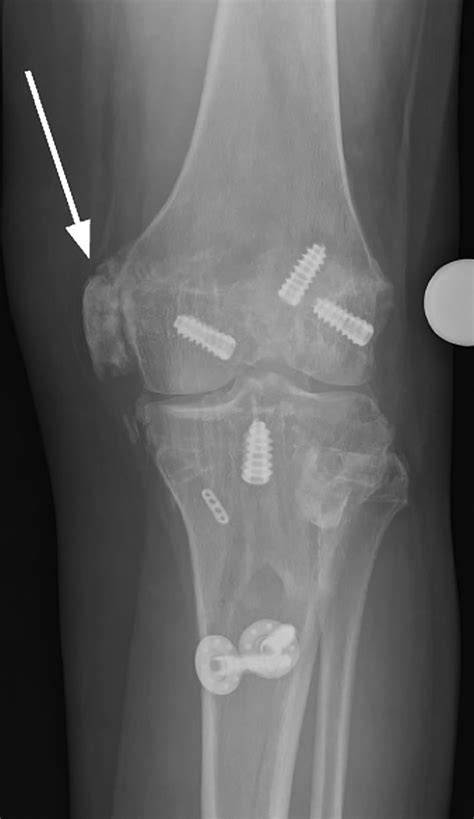

A Pellegrini Stieda Lesion is a rare condition characterized by the calcification of the medial collateral ligament (MCL) of the knee. The MCL is a crucial ligament that provides stability to the inner side of the knee joint. When this ligament becomes calcified, it can lead to pain, stiffness, and reduced range of motion. The condition is named after the Italian surgeon Pellegrini and the German surgeon Stieda, who first described it in the late 19th century.

• Imaging Tests: X-rays, ultrasound, or MRI scans to visualize the calcification and assess the extent of the damage.

• pellegrini stieda lesion xray

• pellegrini stieda calcification